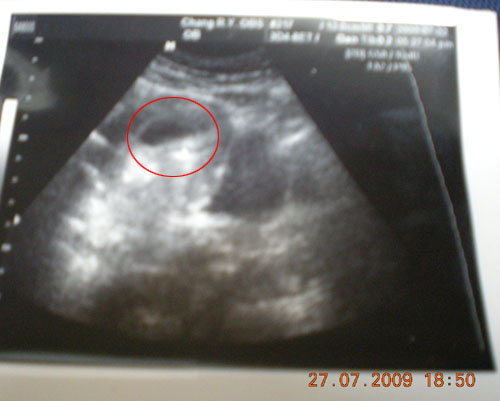

第七週了~BABY有心跳了~我聽醫生弄給我看心跳~因為聲音很好玩~所以我不爭氣的笑了!!

可是有生命在體內跳動呢~好感動~雖然小小的~白色部份就是BABY了~才1.4公分唷^^ 好可愛喔~